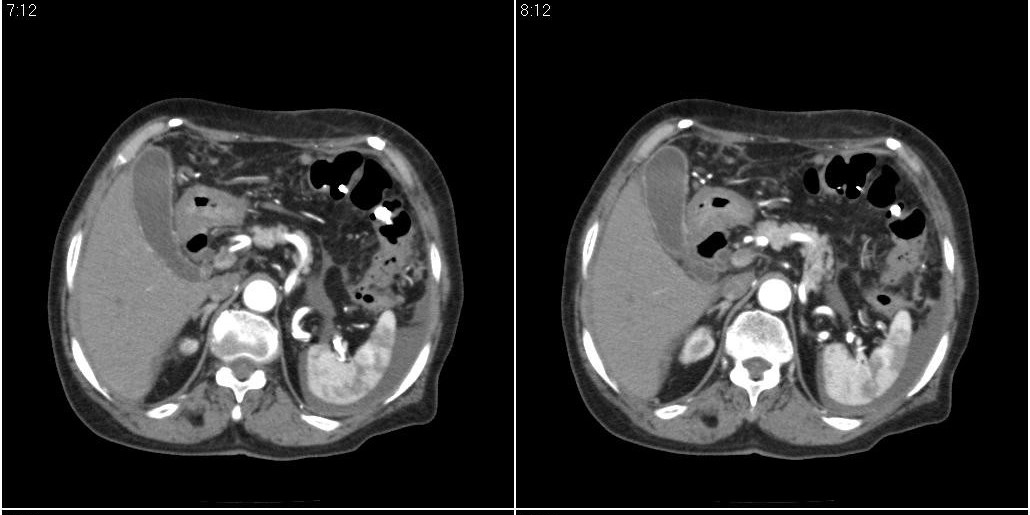

胆囊有问题么,是结石么?胆囊内异常密度平扫30hu左右,增强各期无变化。

胆囊内异常密度影增强各期无变化,考虑泥沙样结石。

胆囊炎,胆结石,胆囊窝积液,胸腹水。

胆囊内稍高密度影,无强化,胆囊壁增厚,周围见低密度影,右侧膈肌角及脾周水样密度,支持胆囊泥沙样结石,胆囊炎、胆囊窝积液,胸腹水。